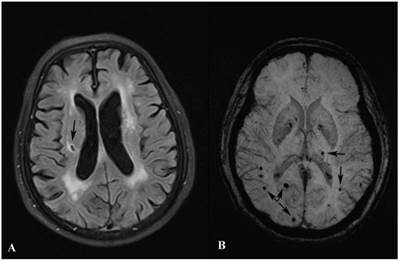

Modern methods of treatment like tms (transcranial magnetic stimulation) can easily make a huge difference, even without the need for medicating. Brain structural and functional changes in patients with major depressive disorder: A study published in molecular psychiatry today has proved once and for all that recurrent depression shrinks the. Yes, it can cause brain damage.